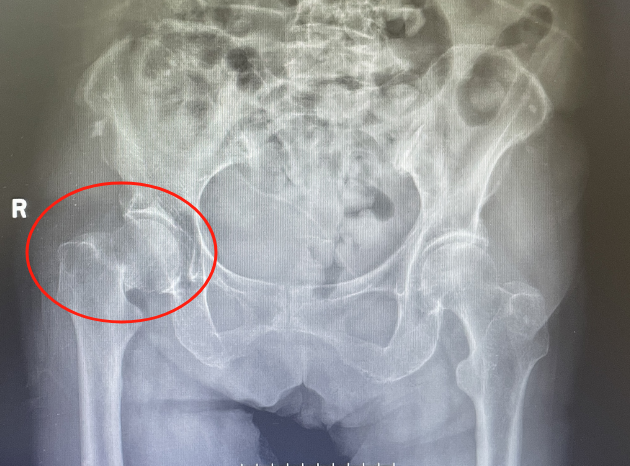

入院后檢查發(fā)現(xiàn)老人右側(cè)股骨頸骨折,更加麻煩的是張奶奶有高血壓病、冠心病、腦梗塞等病史20余年。高齡、基礎(chǔ)疾病多,手術(shù)風(fēng)險(xiǎn)高。但骨折后保守治療,需要長(zhǎng)期臥床,疼痛難忍,吃喝拉撒都要在床上進(jìn)行,并發(fā)癥多,生活質(zhì)量下降?!笆中g(shù)?還是不手術(shù)?”張奶奶的家屬可發(fā)了愁?!白詈玫姆椒ㄟ€是控制內(nèi)科疾病后,幫忙老人盡早手術(shù)治療吧!”經(jīng)過骨科副主任醫(yī)師徐光輝耐心與家屬溝通后,家屬要求積極手術(shù)治療。